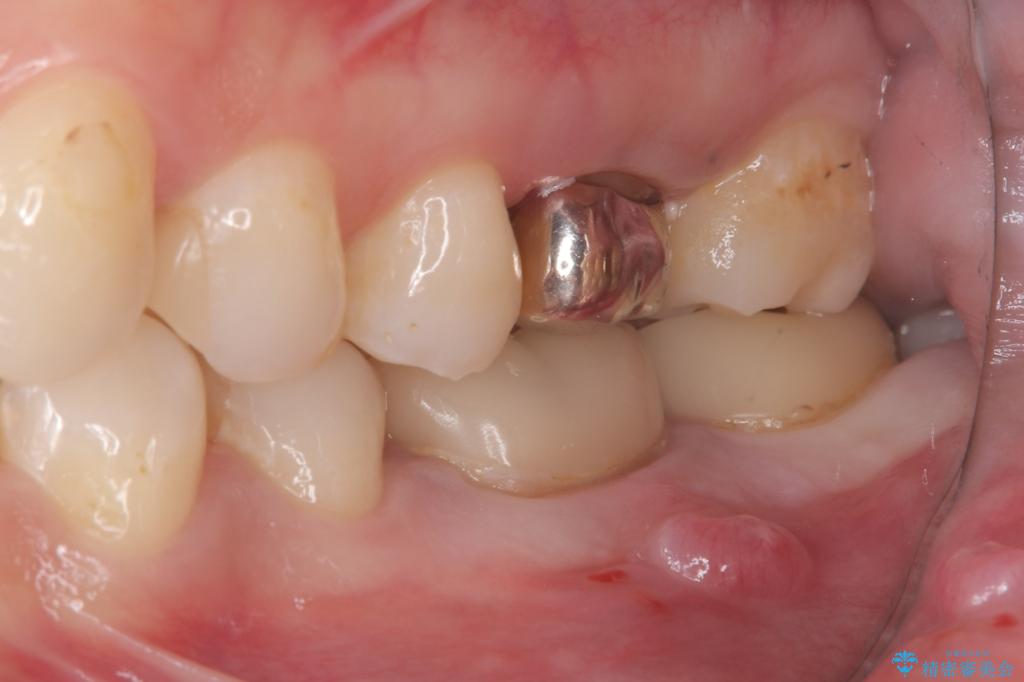

- 主訴:左下6番目の歯の周りが痛くなり、他院で診てもらったが抜歯と言われてしまった。ネットで歯牙移植というものを知りやっている医院を探している。

左下6番目の歯の周りに大きく透過像を認め、再根管治療後の予後が良くない可能性が大きく当院でも抜歯適用歯と説明しました。欠損部に対しインプラント治療や歯牙移植(左下の親知らずの移植)、ブリッジを提案し、歯牙移植を行うこととなりました。

保存が難しい左下6番目の歯を抜歯し、左下8番目の歯(親知らず)を抜歯窩に移植しました。歯牙移植後の動揺防止のため暫間固定を行っています。